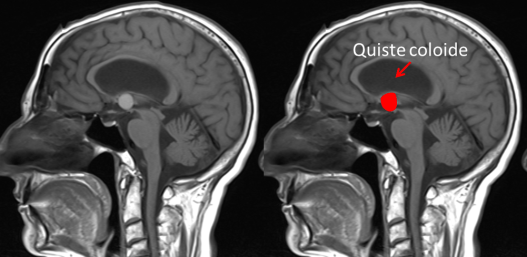

En el estudio con resonancia cerebral se puso de manifiesto la existencia de un quiste coloide del III ventrículo que había pasado inicialmente desapercibido en la TAC cerebral.

La presentación clínica de un quiste coloide del III ventrículo puede ser la misma que la de una hidrocefalia a presión normal (alteración de la marcha, incontinencia urinaria y alteración cognitiva). Los quistes coloides del III ventrículo se suelen ver en la TAC cerebral sin contraste porque en 2/3 de las ocasiones son hiperdensos pero en 1/3 de los casos como éste caso son isodensos/hipodensos y pueden pasar desapercibidos inicialmente. Además hay que tener en cuenta que cuando se introduce contraste en la TAC cerebral puede no verse tampoco. Únicamente tras la realización de la resonancia cerebral se pudo diagnosticar por su hiperintensidad en secuencias T1 (imagen 3) y su hipointensidad en secuencias en T2.

En la imagen 4 se puede intuir la presencia del quiste coloide que inicialmente había pasado desapercibido.